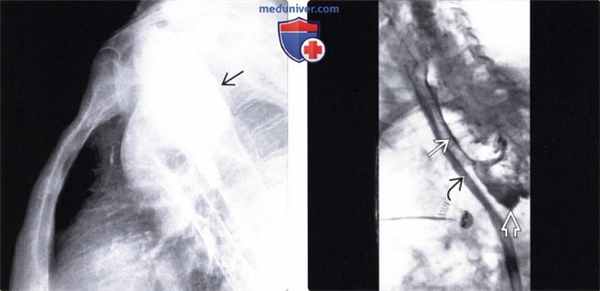

(Слева) При рентгенографии органов грудной клетки, выполненной пожилой женщине после попытки введения зонда для энтерального питания, определяется тень извитой формы в проекции средостения.

(Справа) На рентгенограмме, выполненной после проглатывания бариевой взвеси, у этой же пациентки визуализируется большой дивертикул, спускающийся далеко вниз.

(Слева) На рентгенограмме в боковой проекции у этой же пациентки визуализируется дивертикул большого размера, расположенный в области перехода глотки в желудок, который смещает кпереди пищевод и трахею.

(Справа) На рентгенограмме, полученной во время рентгеноскопии у пожилого мужчины с жалобами на боль после попытки введения зонда для энтерального питания, определяется скопление газа и водорастворимого контраста позади тени пищевода и в проекции средостения. Полоска контрастного вещества находится параллельно стенке проксимальных отделов пищевода. У пациента была подтверждена перфорация дивертикула Ценкера.